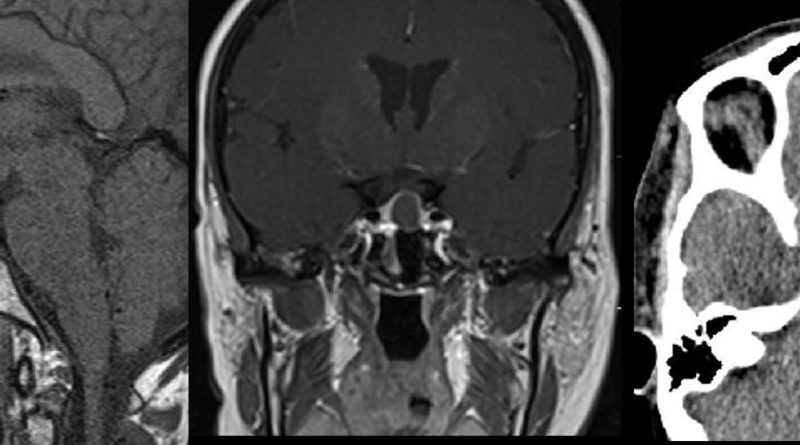

61 yaş, K

15-20 yıldır süren baş ağrıları, sağ göz görme alanında tam kayıp

Tuberkulum sella meningiomu